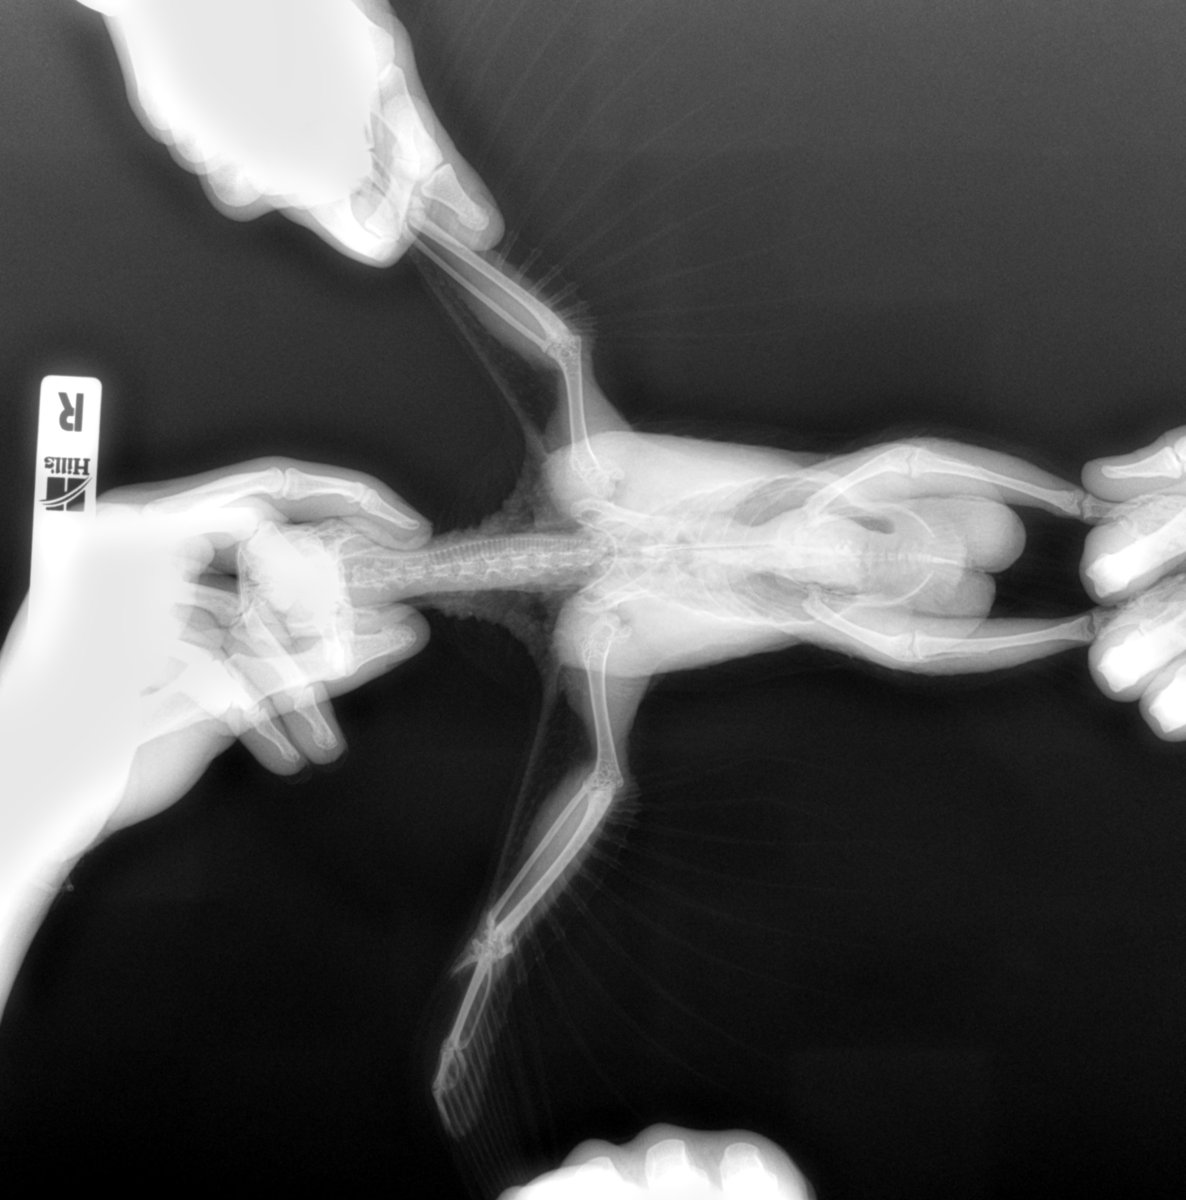

KamaRo Опубликовано 18 января, 2019 #10 Опубликовано 18 января, 2019 @Alexandr48 после приобретения новой птицы (любой) необходим карантин, который заключается в проведении обследования - как уже сказали по паразитологии, общих болезней с человеком (орнитоз, сальмонеллез ,туберкулез), микоплазмоз, посевы мазков из зева и клоаки и в вашем случае необходимое - рентген в двух проекциях. У птиц много чего проходит в скрытой форме и когда появятся симптомы считайте, что вы опоздали причем не несколько лет. По вашим фото сказать о характере опухоли ничего нельзя - никто не обладает рентгеновским зрением, а гадание ни к чему хорошему не приведет. Снимок должен быть вот таким (четко и в макросъемке, вот тогда вообще о чем то можно говорить):